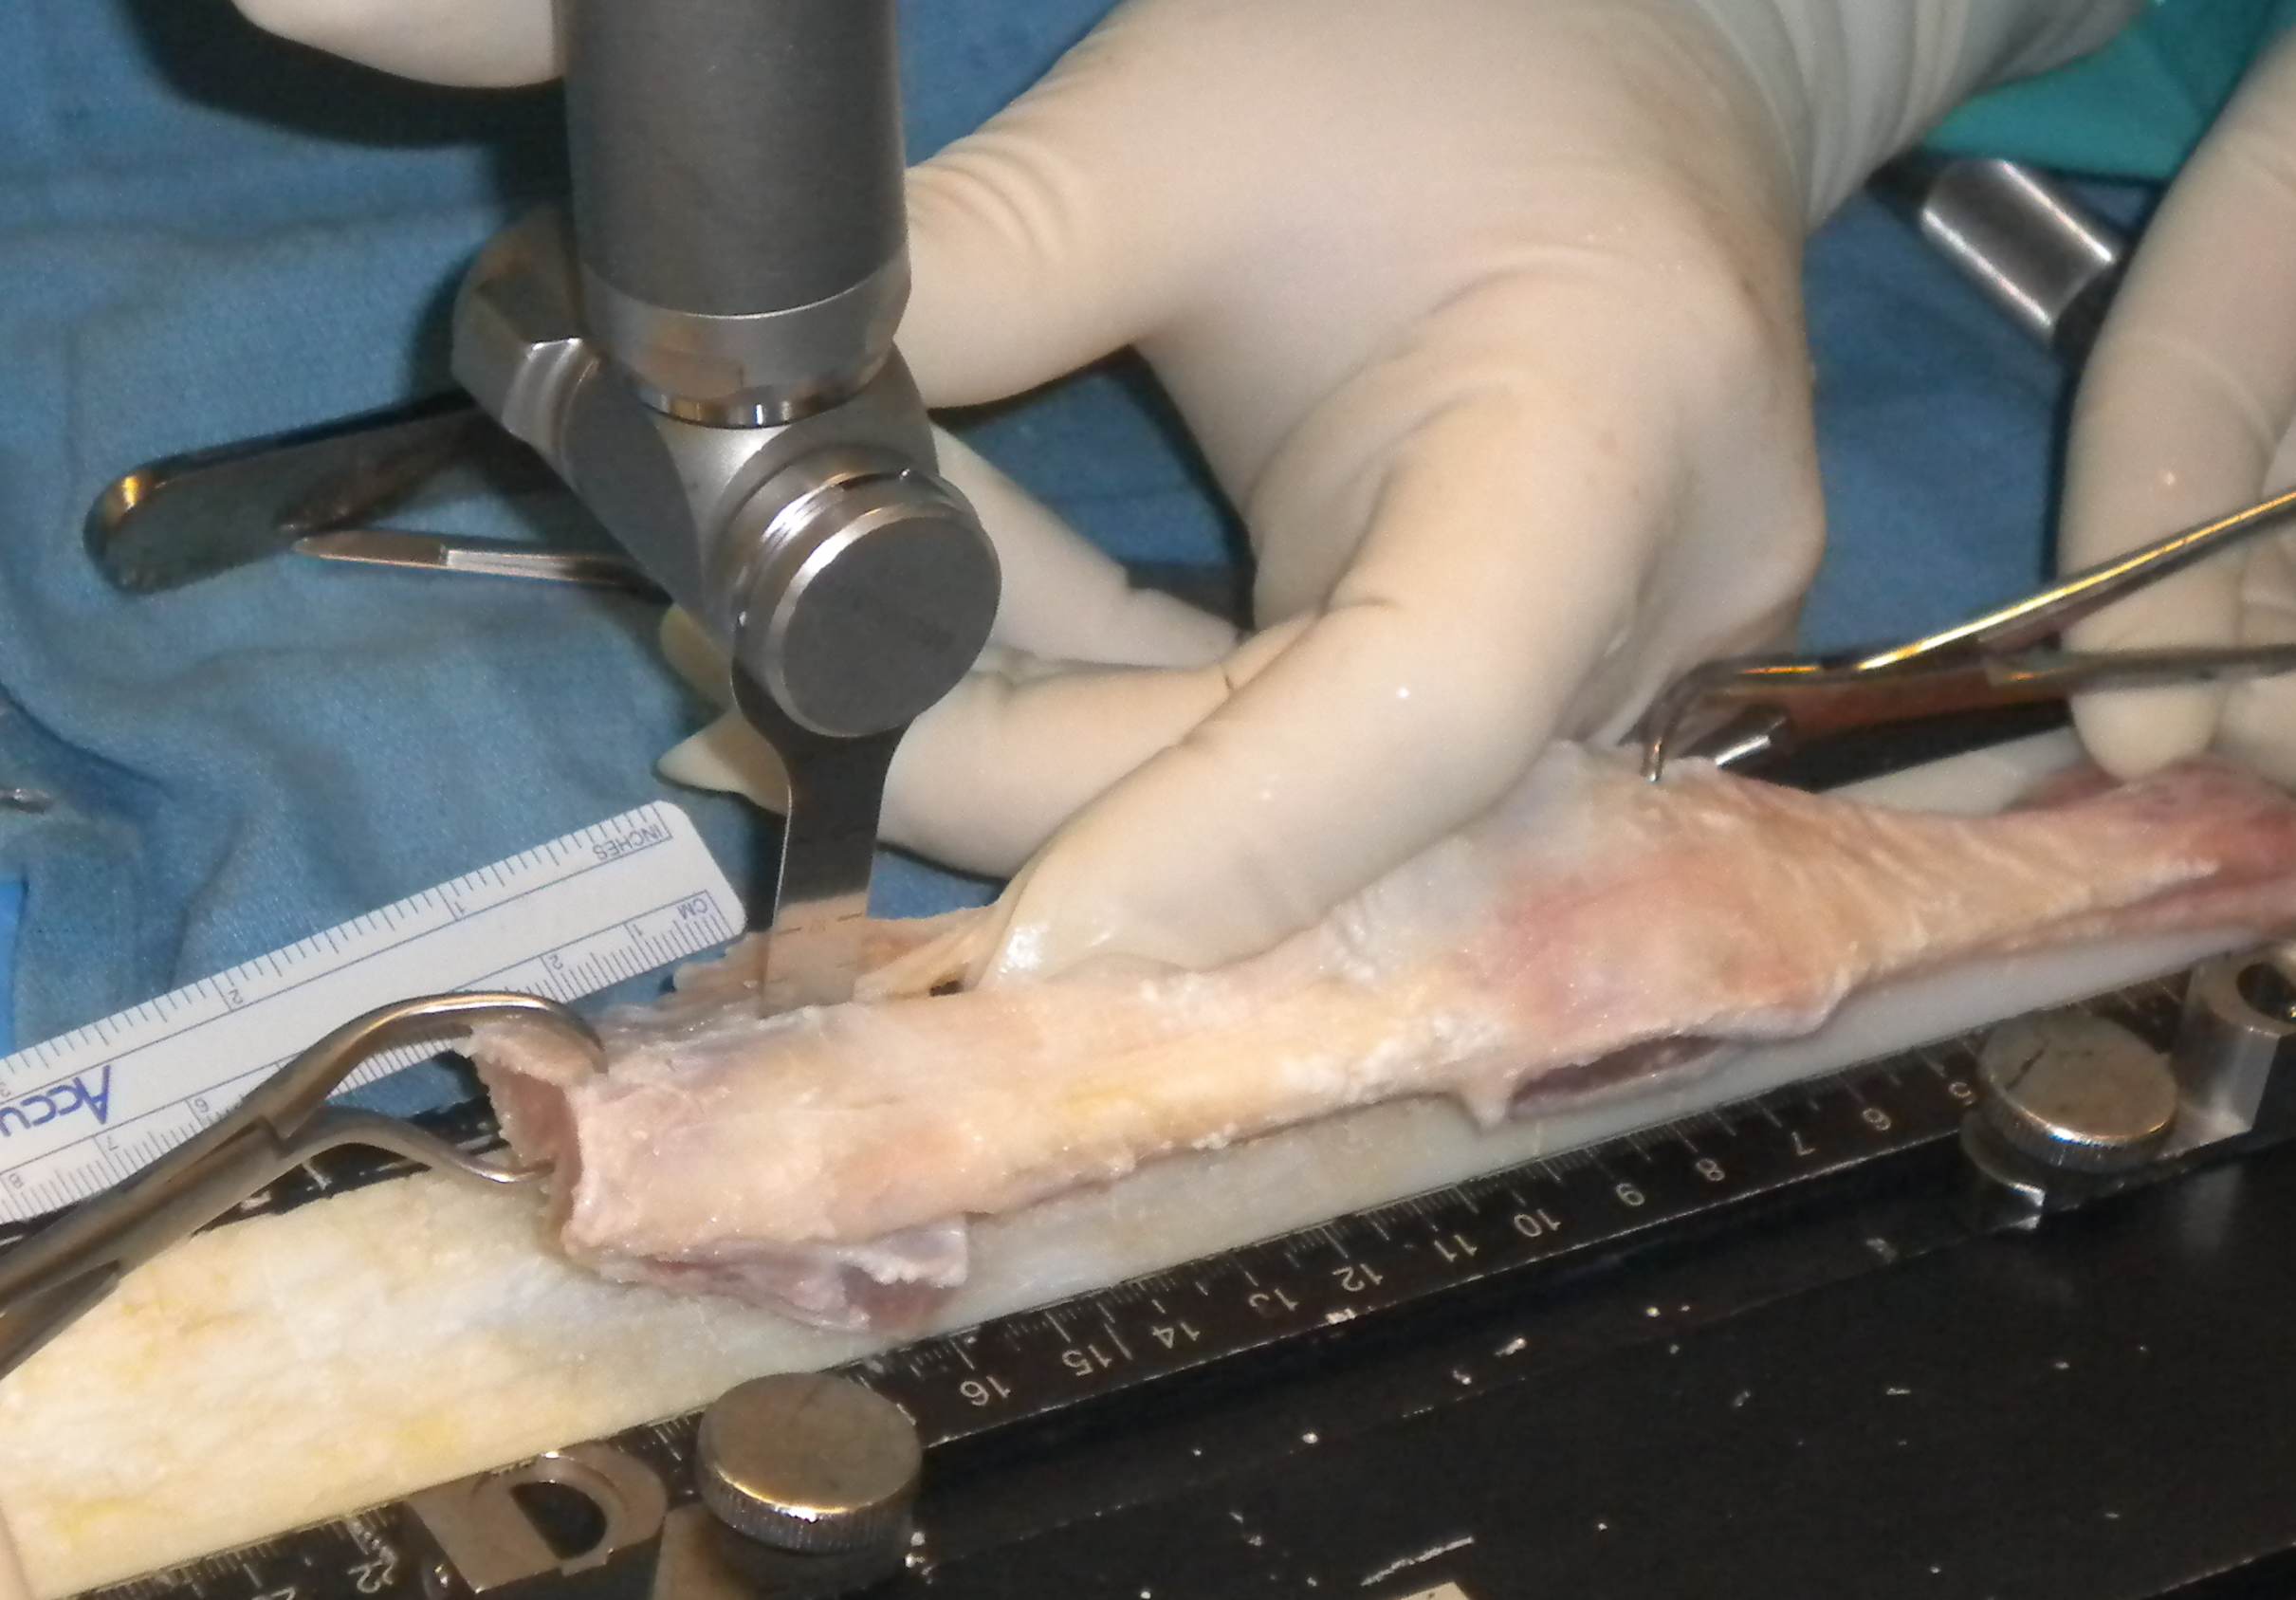

Cut tendon with knife

- 10 mm thick in women

- 12 mm thick in men or revisions

- adjust to patient's size and needs

Cut soft tissue on patella / tibial tuberosity ends

- usually narrow graft so becomes 10 mm wide

- can make 12 mm wide in revision setting

- cut with saw on each side

- turn and cut so is 10 mm thick

- ensure this end fits nicely through 10 mm / 12 mm tube

- this will be the passing end